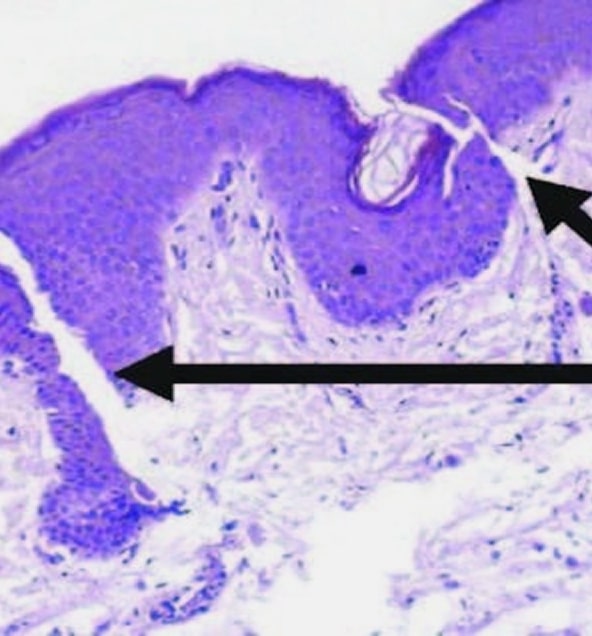

- Dies geschieht in der dermal-epidermalen Junktionszone (DEJ).

- Dieser Dermisbereich mit flacher DEJ ist die Zieltiefe für die Mikronadel. Siehe Pfeile, wo die Mikrokanäle gebildet werden

- Dies geschieht in der dermal-epidermalen Junktionszone (DEJ).

- Dieser Dermisbereich mit flacher DEJ ist die Zieltiefe für die Mikronadel. Siehe Pfeile, wo die Mikrokanäle gebildet werden